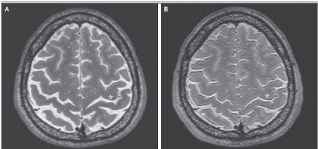

In addition to parts of the brain becoming squished for long periods of time, space travel may also “rewire” our brains. Researchers imaged astronauts’ brains to see the structure of the brain before and after 6 months of space flight. Through these images, researchers learned that white matter, the material in the brain that helps relay information and signals quickly and efficiently, was significantly decreased in the part of the brain responsible for motor control and a region of the brain responsible for balance, the insular cortex [2]. These effects never went away. Astronauts may experience this loss of white matter due to decreased need for balance and movement while floating around in zero gravity, but the fact that the white matter never recovers means that astronauts might struggle with movement for the rest of their lives while back on earth